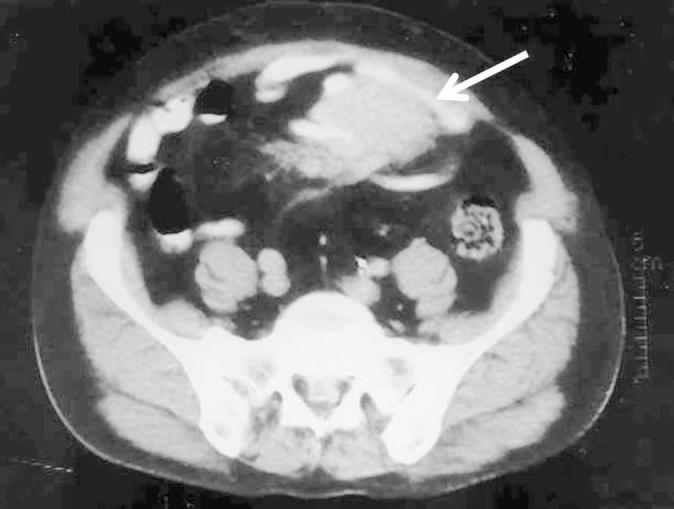

Mesenteric Fibromatosis Mimicking Tumor Recurrence Following Radical Cystectomy and Bladder Replacement.

We report an unusual case of benign tumor mimicking tumor recurrence following radical cystectomy and bladder replacement for high grade urothelial carcinoma.